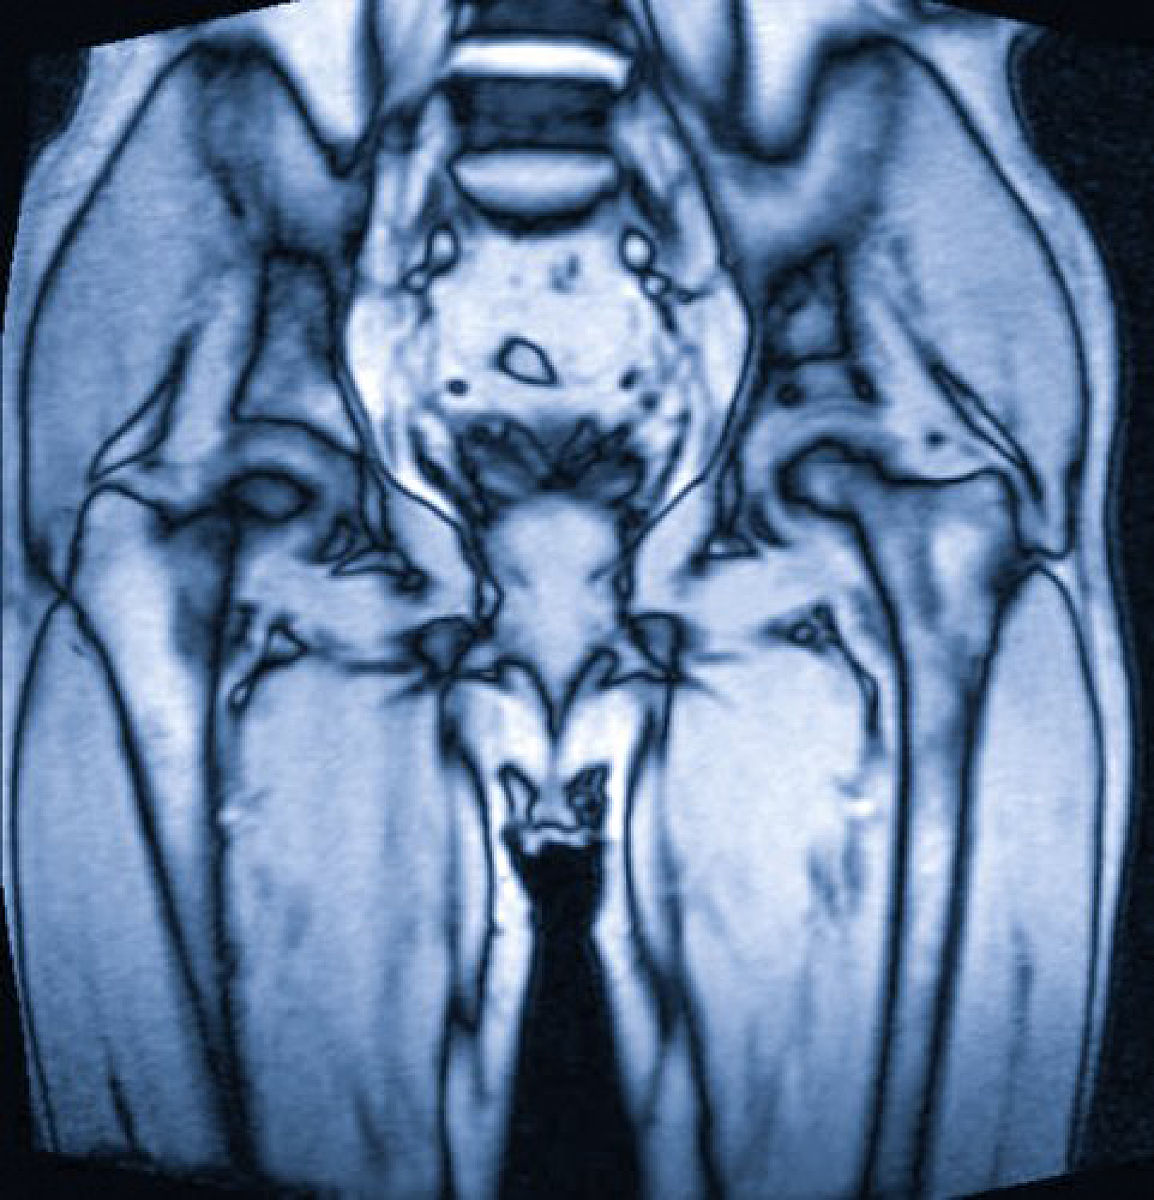

盆骨疼痛的原因可能有以下几种:

盆骨疼痛的原因:受凉、月经期、过度劳累等,如何缓解?